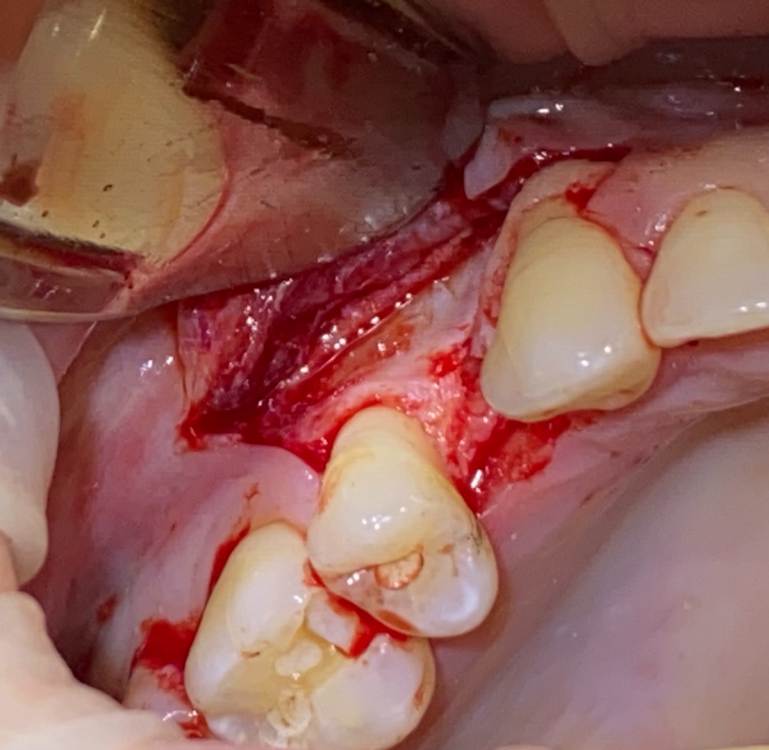

Женька Опубликовано 17 июня, 2021 Автор Поделиться Опубликовано 17 июня, 2021 Как вы наверное уже догадались я не осилил этот кейс. Точнее осилил, но не как планировал изначально. Сделал маленькую сосиску, уже прогнозирую, что мало что там вырастет у меня. Пытался собрать ауто, сначала скрёб бузеровским распатером, потом решил сделать «ложе» для имплантата и забрать кости там. Насобирал мало конечно же. Сделал какое-то подобие штайгмановского лоскута кмк, хотя наверное это не так. Подшил мембрану к надкостнице, хотел чтобы надкостница была в нахлест на мембране, вышло «в стык». Утрамбовал апатос, подшил под нёбный край. Плотненько получилось, даже понравился вид ( а фото забыл сделать) Натянул лоскут, хотя прежде мобилизовывал хорошо как показалось. Снова мобилизовал, ушил. Уже жду когда это развалится. Соотношение ауто/ксено примерно на уровне 80/20(думаю даже меньше). Думаю, что надо было дистально лоскут ещё на зуб продлевать. Но есть и хорошие новости, я кажется понял, каким пациентам я буду отказывать в лечении... ну и лоскут не порвал, это уже уровень для меня. Ссылка на комментарий

Женька Опубликовано 17 июня, 2021 Автор Поделиться Опубликовано 17 июня, 2021 (изменено) @Карен Аванесов с того, что работа должна приносить удовольствие. Мне удовольствие приносят только чужие кейсы... Какой бы случай не попал ко мне я никогда не доволен своим результатом. Ну может за редким исключением. Но в основном не доволен. Так и тут. Планировал и имплантат и нкр и шминус-синус...на деле, извините за выражение, обделался. Даже шаблон под пилотное сверление был... поставь я имплантат, в любом случае сст бы не обошлось, тк шероховатая поверхность была бы вестибулярно оголена. говоря об удовольствии... наверное это всё от недостатка знаний... 16 минут назад, Irouil сказал: Пока Увы Изменено 17 июня, 2021 пользователем Женька Ссылка на комментарий